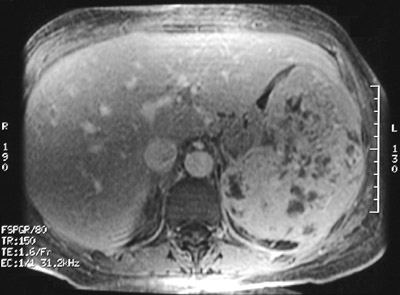

| There is a heterogenous splenic mass seen in the abdominal CT scan above. This large mass expands the spleen. Histologically, it was an angiosarcoma. In the T1 weighted MRI scan below can be seen areas of increased signal intensity characteristic for hemorrhage in a vascular neoplasm. A T2 weighted MRI scan is shown at the bottom in which the hemorrhagic-vascular areas appear darker. |